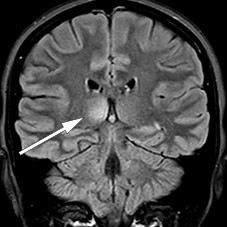

A follow-up MRI one month later showed a new non-enhancing lesion in the right thalamus (Figure 2) as well as two new, small, enhancing lesions in the medulla at C5, C6 and possibly also Th5. The infratentorial lesions had resolved completely, and those in the medulla oblongata were reduced.

Figure 2 Right thalamic lesion on coronal MRI with FLAIR (fluid-attenuated inversion recovery).